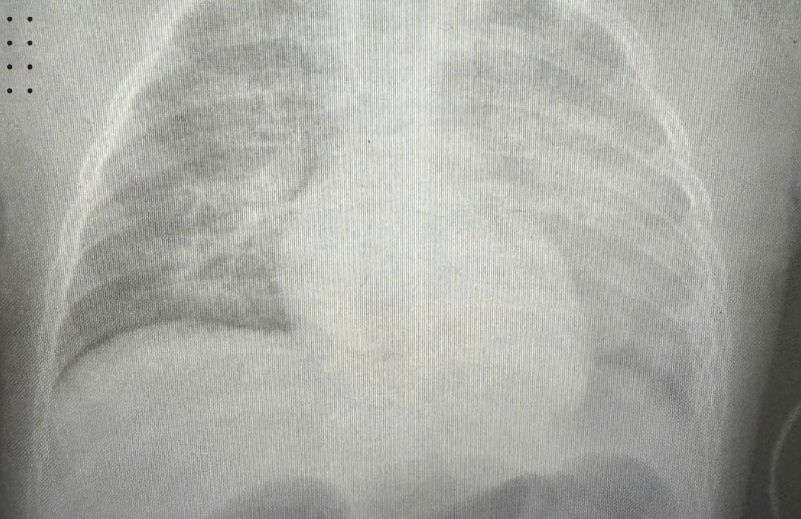

Một biến chứng phổ biến của bệnh phổi tắc nghẽn mạn tính

Hút thuốc lá âm thầm tàn phá hệ hô hấp, dẫn đến hàng loạt bệnh phổi nguy hiểm như bệnh phổi tắc nghẽn mạn tính (COPD), hen phế quản, nhiễm trùng đường hô hấp.